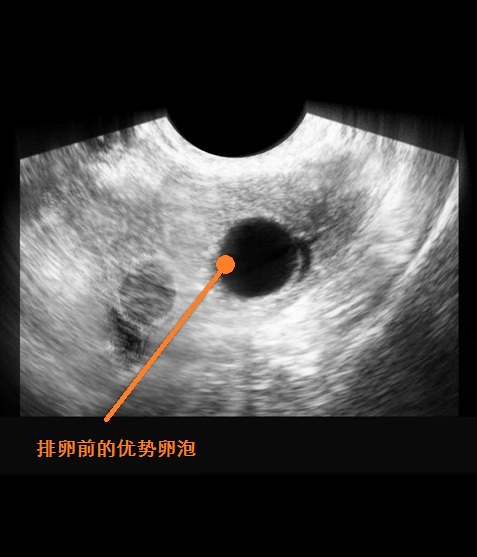

排卵通常发生在月经周期的第14天,所以,本周末你的排卵期就会开始,怀孕计划进入倒计时。别忘了,甜蜜的夫妻关系,永远是生育健康宝宝最重要的基础。,受精卵从输卵管进入到子宫,在子宫中继续生长。受精一周后胚胎会分泌一种激素,这种激素能够帮助胚胎埋入子宫内膜,使受精卵就正式安顿下来,进行有规律的发育。

由于排卵通常发生在月经周期的第14天,如果你两周后月经还没有按时的到来,你就可能已经怀孕2周多了。